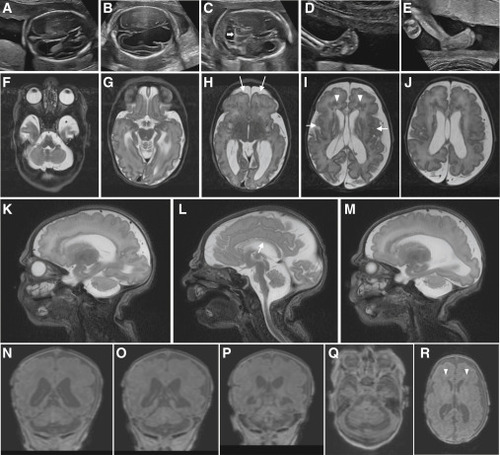

Clinical imaging of the family B and family E probands who harbor bi-allelic variants in SNAPIN (A–E) Prenatal ultrasound imaging of the family B-II:3 fetus showing progression of ventriculomegaly at (A) 19 to (B) 21 weeks of gestation, with disruption of ventral parenchyma at 21 weeks; (C) cerebellar hypoplasia at 21 weeks of gestation (white horizontal arrow); and (D and E) progression of clubfeet at (D) 19 to (E) 21 weeks. (F–R) Brain MRI of the family E-II:3 proband, born at 38 weeks of gestation, at 3 days of age showing a complex brain malformation including microcephaly with simplified gyral pattern (arrows, H), polymicrogyria (arrows, I) (G–R), thin corpus callosum (arrow, L), bilateral enlargement of lateral ventricles (H–J, N, and O), prominent periventricular white matter lesions suggestive of mixed subcortical heterotopias (arrow heads, I and R), and pronounced pontocerebellar hypoplasia (F, L, and Q). (F–J) T2-weighted axial images, (Q and R) T1-weighted axial images, (K–M) T2-weighted sagittal images, and (N–P) T1-weighted coronal images.